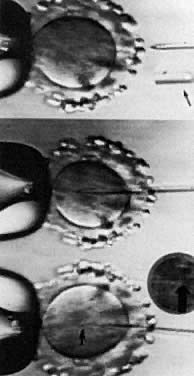

Under visualization on the stage of an inverted microscope, oocytes in culture medium droplets under oil are held and micromanipulated with specially prepared holding and injection pipettes. The oocyte is immobilized with gentle suction applied by the holding pipette, and the injection pipette is used to incise the zona pellucida (ZP), deposit several sperm in the perivitelline space, or inject a single sperm directly into the ooplasm. These techniques can be classified as: zonal, subzonal, and intracytoplasmic procedures. Although known by many names such as zona drilling, subzonal insertion, and direct egg injection, the following terms are used in this chapter: partial zona dissection (PZD), subzonal injection (SUZI), and intracytoplasmic sperm injection (ICSI) (Fig. 2).

Fig. 2. Micro-assisted fertilization. Metaphase II oocyte illustrating microsurgical-assisted fertilization techniques: PZD, incision in ZP to facilitate sperm entry: SUZI, injection of a few sperm into perivitelline space; ICSI, injection of a single sperm into the ooplasm.

Fig. 3. Intracytoplasmic sperm injection. Top: metaphase II oocyte just before insertion of micropipette containing single sperm (magnified sperm head in pipette, arrow). Middle: micropipette inserted into ooplasm. Bottom: single sperm in center of ooplasm after injection (arrowhead; magnified sperm head inset, arrow).